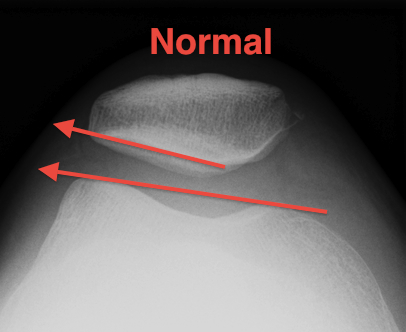

A. Blumensaat's line / Inaccurate

Knee flexed to 30o

- line should just touch inferior pole of patella

- pole above line - alta

- pole below line - baja